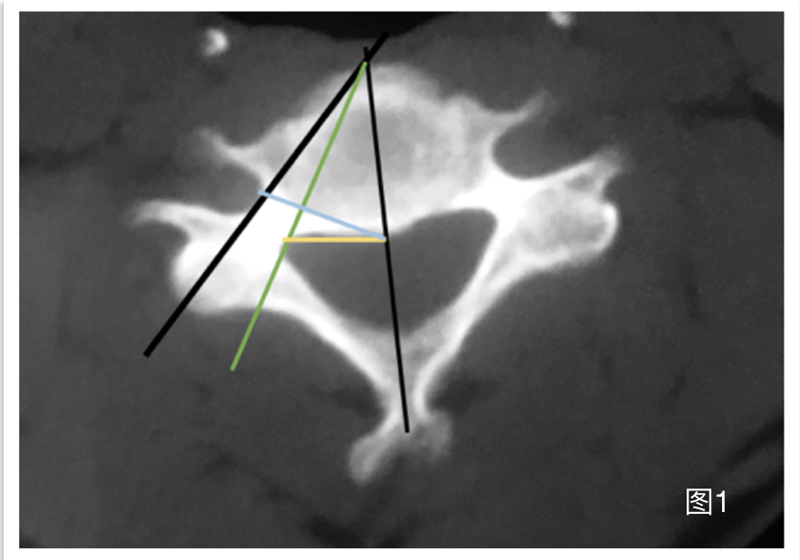

据文献报道,虽然ACDF术引起血管损伤的概率只有0.3%-0.5%,但是只要出现椎动脉等颈部血管的损伤,后果往往十分严重:可能会导致脑供血不足,严重的损伤甚至会引起患者的死亡。对此,Park等人通过对椎间孔的影像学研究发现,如果手术过程中医生需要对钩椎关节进行减压,从椎体的中线向两侧减压不超过13mm,可以在一定程度上避免对椎动脉的损伤并获得最大程度的减压范围(图1)。

图1